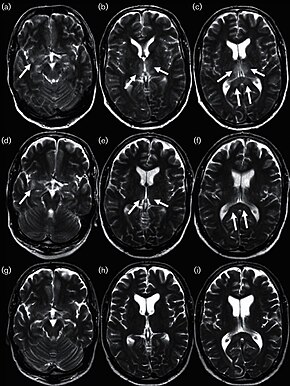

Influenza encephalitis MRI

In some cases, an autoimmune response to an influenza infection may contribute to the development of Guillain–Barré syndrome.[171] However, as many other infections can increase the risk of this disease, influenza may only be an important cause during epidemics.[171][172] This syndrome has been believed to also be a rare side effect of influenza vaccines. One review gives an incidence of about one case per million vaccinations.[173] Getting infected by influenza itself increases both the risk of death (up to 1 in 10,000) and increases the risk of developing GBS to a much higher level than the highest level of suspected vaccine involvement (approx. 10 times higher by recent estimates).[171][174]